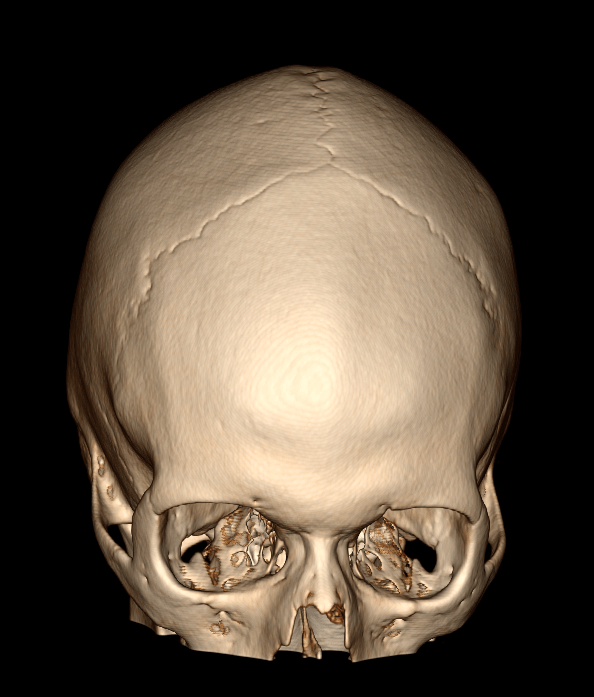

A tomografia de crânio é um exame não invasivo de diagnóstico por imagem que possibilita o estudo do encéfalo, ossos da face e mandíbula. Os equipamentos de tomografia fazem diversos cortes (imagens), cada “corte” refere-se a uma imagem individual e corresponde a uma “fina fatia” do segmento do crânio a ser analisada. Assim sendo, é possível recompor por meio de técnicas todos os segmentos obtidos, produzindo uma série de imagens finais que serão analisadas pelo médico radiologista, com muita qualidade e precisão. Em algumas situações, é solicitado o uso de contraste iodado – via endovenosa-, para uma visualização mais detalhada da área desejada e estruturas vasculares.

É um excelente método de imagem para observar fraturas e lesões hemorrágicas.